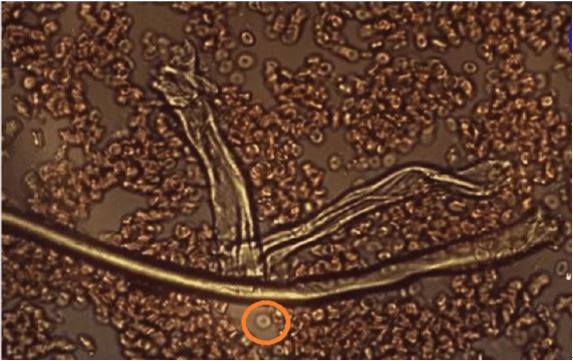

以下は、顕微鏡で見た典型的な健康な赤血球の画像で、血液がどのように見えるべきかを示している。凝固や異物が入っているわけではない。

以下は、実験的なCovidワクチンを注射された人の写真である。

血液が凝固し、形の悪い赤血球がまとまっている。画像で○に囲まれているのは健康な赤血球で、グラフェン繊維と並んでいる数少ない赤血球である。

赤血球の大きさに比べて、グラフェン繊維の大きさがわかるだろう。このサイズの繊維は、毛細血管を塞いでしまう。また、グラフェン繊維は中空で、赤血球を内包していることもわかる。